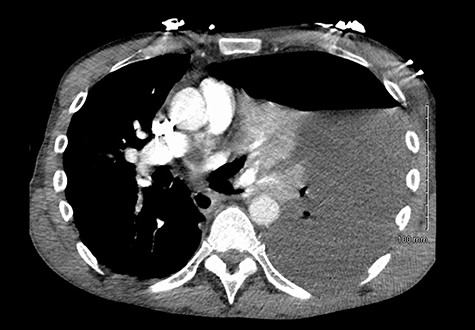

(Left) Contrast in stomach and pleural fluid are iso-dense confirming a fistula; (Right) neck of hernia in the diaphragm.

There are no specific signs of GPF on a plain film. Surrogate signs of a diaphragmatic defect include an intrathoracic stomach or nasogastric tube and elevation of the hemidiaphragm [5]. Notably, up to 66% of diaphragmatic injuries are missed on a plain film [5]. Although CT has a specificity of up to 99% for diagnosing diaphragmatic defects [5], it is again not specific for GPFs. Based on our institutional experience, the diagnostic yield for a GPF can be increased with modifications to CT protocols. The administration of both oral and intravenous contrast allowed visualisation of contrast extravasation from the stomach into the pleural cavity. Clamping of the chest drain and keeping the patient supine for an hour after consumption of oral contrast ensured that there was maximal accumulation of contrast in the pleural cavity. The gold standard for diagnosis remains direct intra-operative visualisation [2].